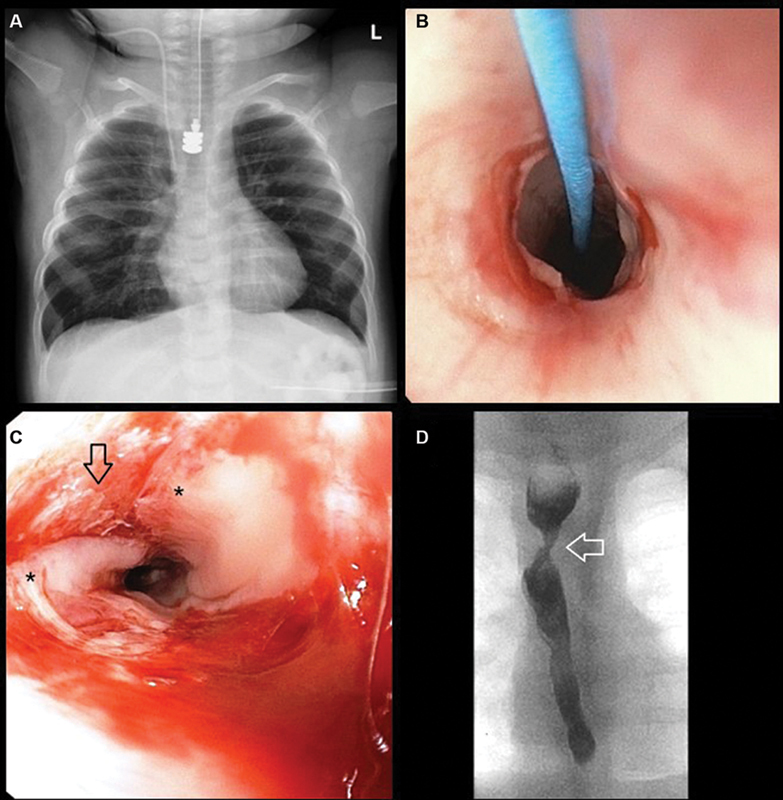

Esophageal atresia (EA) repair can be complicated by associated malformations such as a tracheobronchial remnant in the distal esophagus. We describe our experience with a patient found to have long-gap EA with a distal cartilaginous ring who was managed using a combination of esophageal lengthening and magnetic compression anastomosis. A 5-month-old girl was referred to us from an outside hospital with type C EA including a very high upper pouch. She had undergone a prior thoracotomy with fistula ligation during which a clip was placed on the lower esophagus, leaving a 2-cm diverticulum on the trachea and a short lower esophageal pouch. Upon endoscopic evaluation at our center, we found a tracheobronchial remnant in the lower esophagus between the clip and the carina. An open thoracotomy was performed to approximate the esophageal pouches and a magnet anchor (Connect EA, Myka Laboratories, San Francisco, California, United States) was placed retrograde through the distal esophageal cartilaginous ring into the lower pouch. On postoperative day 8, after adequate growth and decreased pouch tension, a second magnetic anchor was placed endoscopically to the upper pouch to mate with the previously placed lower pouch anchor. The anastomosis formed within 14 days. Due to the tracheobronchial remnant, the device did not pass distally and was removed endoscopically. On postoperative day 8, balloon dilation of the anastomosis and tracheobronchial remnant was performed. Subsequently, the patient required a total of 6 dilations in an 18-month follow-up. This case report illustrates the utility of using magnets to create an esophageal anastomosis in complex cases of EA with concomitant esophageal malformations. The parents of the patient gave their written consent to publish this technical report.